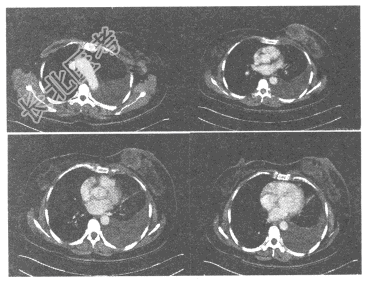

- 单项选择题女,65岁, 发现左乳肿块,质硬, 左腋窝可扪及肿大淋巴结,CT增强扫描如图所示, 其诊断应考虑为

A、乳腺囊性增生症

B、乳腺纤维腺瘤

C、乳腺癌

D、乳腺导管内乳头状瘤

E、乳腺脂肪坏死